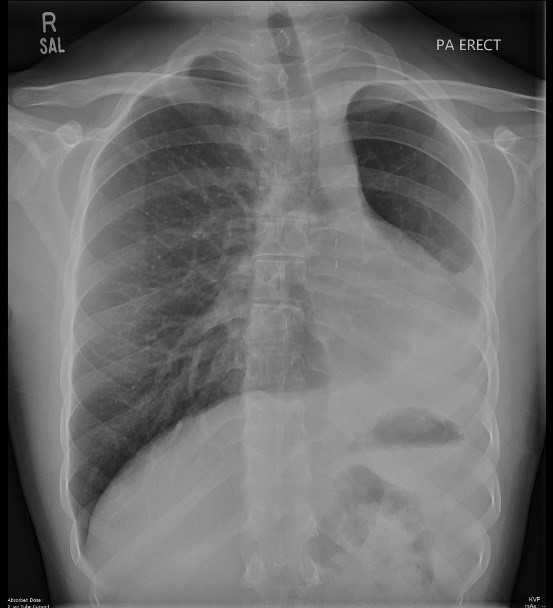

A 34-year-old textile worker presented with fever, cough, and weight loss of 5 kg in 3 months. Upon arrival in emergency, he was short of breath and oxygen saturation was 75% on room air.

Name two laboratory tests done in this case, which helped us diagnose this case within 24 hours.

Question Image